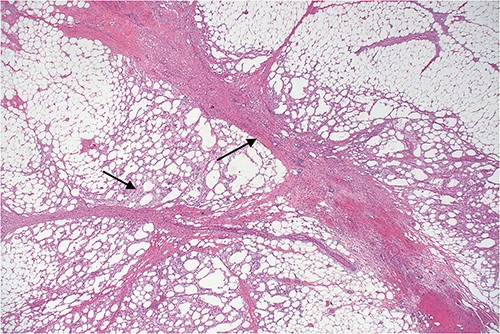

Lower power view of fatty tissue demonstrating a broad band of septal fibrosis, indicating a chronic inflammatory process. Adjacent fat is chronically inflamed and contains a dense infiltrate of foamy histiocytes and some lymphocytes, typical of fat necrosis.